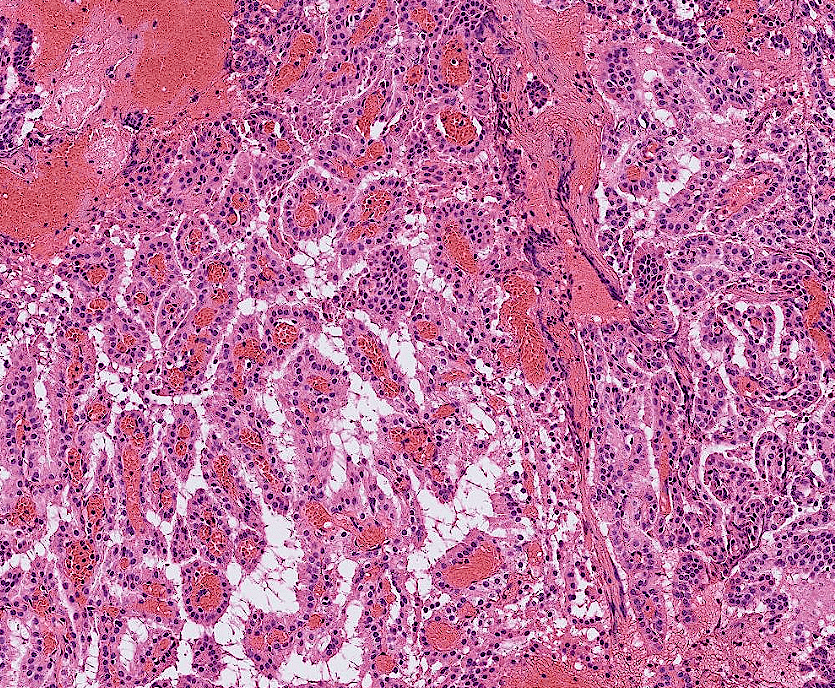

colon cancer